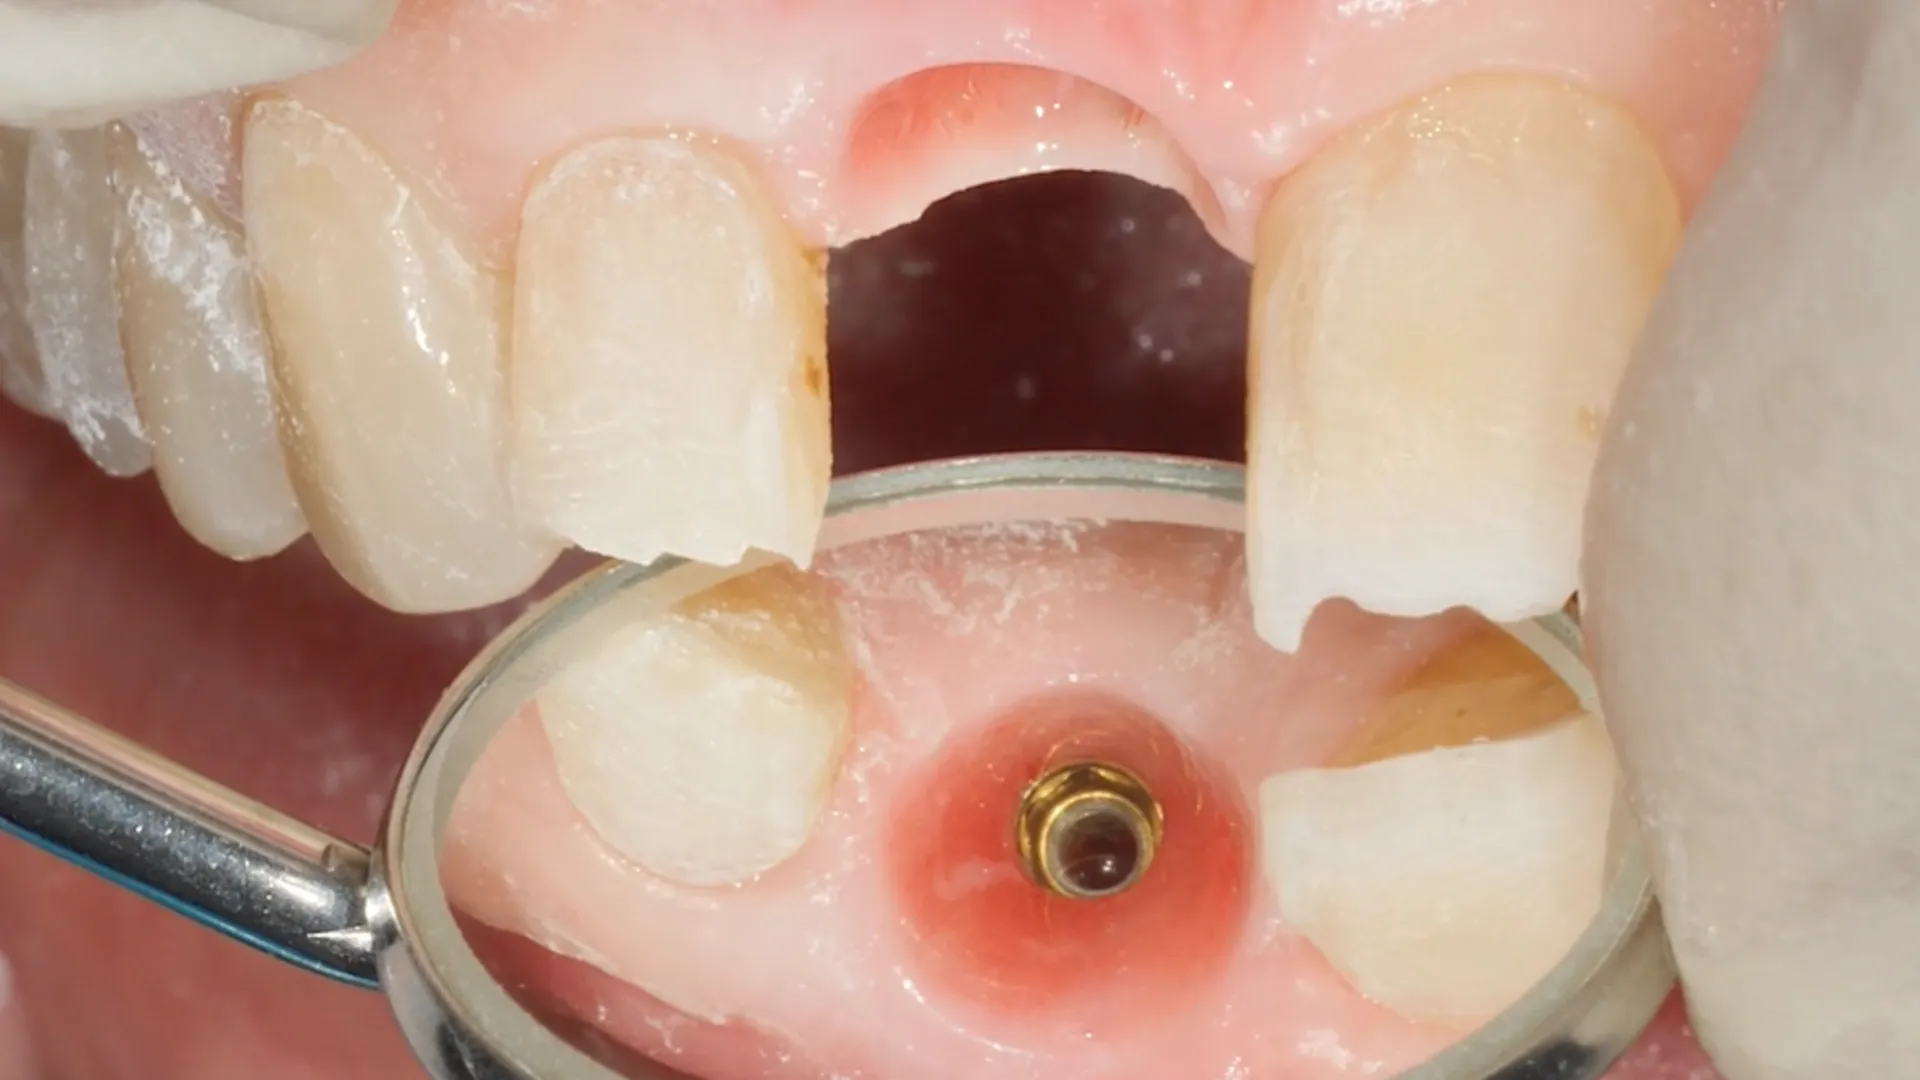

Immediate provisionalization. (A) Connection of a 15 angled abutment

Immediate provisionalization. (A) Connection of a 15 angled abutment Provisionalization The provisionalization strategy will vary depending on the initial condition of the tissues, the need for reconstructive procedures,. Summary this chapter outlines the use of provisionals to prosthetically guide soft tissue healing and to improve the soft tissue. This article describes and discusses the various options for provisionalization in implant dentistry. Clinicians should be aware of the different. Provisionalization is. Provisionalization.